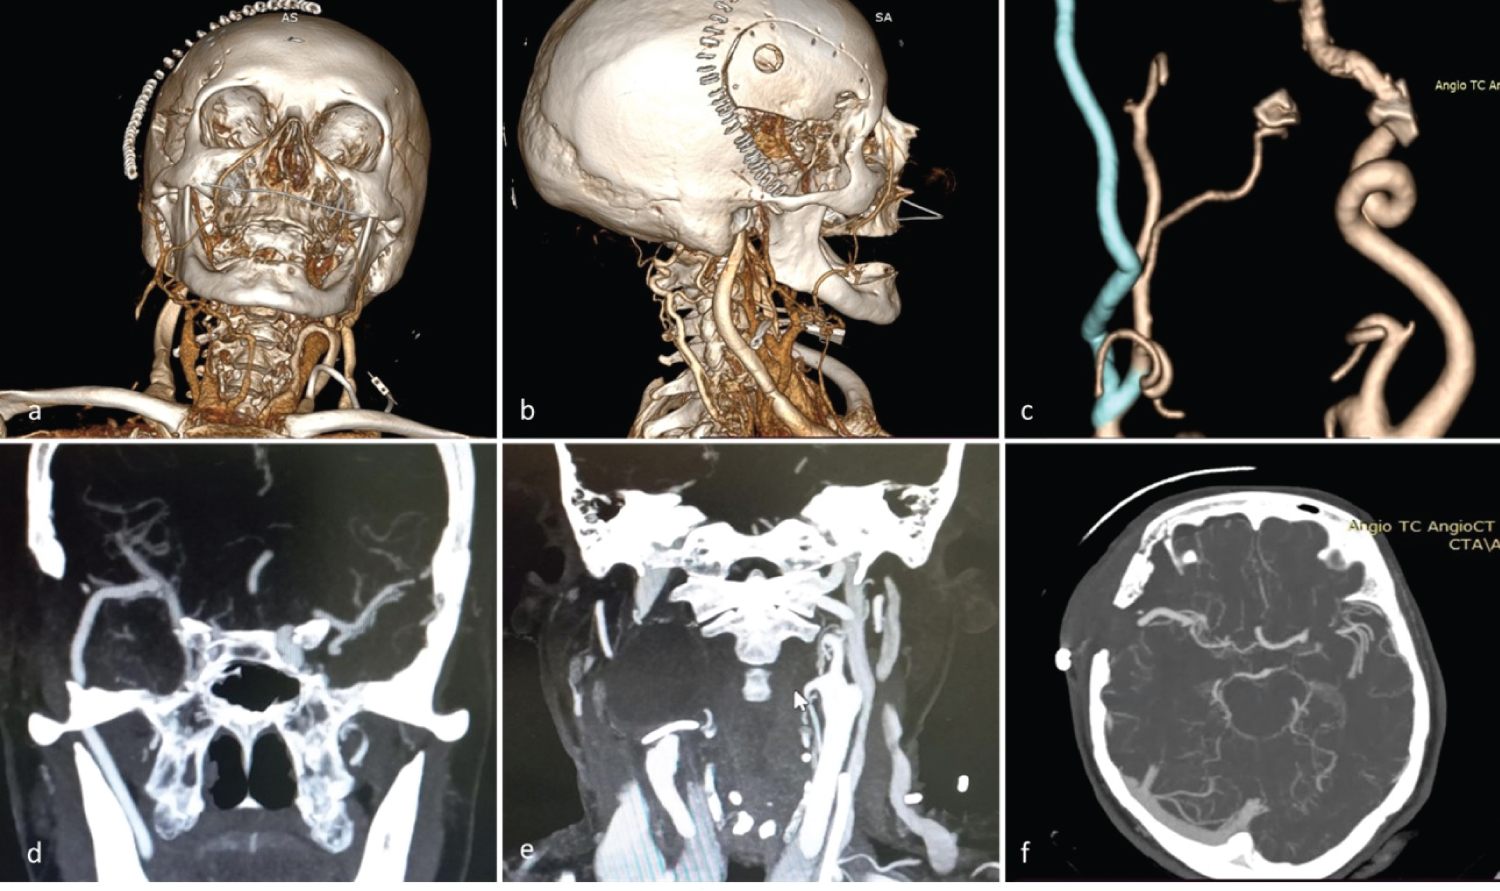

A 60-year-old female patient, natural and from Cajamarca, Peru, with no relevant pathological history, no surgical or family history, presenting with a sensation of pulsatile mass in the upper cervical region for 4 years that progressively increased in size. The patient reported difficulty swallowing, cervicalgia and headache, so she went to the cardiovascular surgery office of a national hospital in Lima where the diagnosis of an aneurysm of the cervical segment C1 of the internal carotid artery was made, which is why she is referred to neurosurgery for treatment. CT angiography and craniocervical angiography studies were performed in which the right extracranial aneurysm measuring 32 × 28 mm at level C1 was evidenced (Figure 1). To determine the anatomy of the donor vessels, vascular studies of the upper limbs were performed (Figure 2).

Figure 1: a,b,c) Cervical CT angiography show an extracranial internal carotid artery aneurysm of 32 × 28 mm. a) The upper end of the aneurysm partly behind the mandible; b) Tortuous cervical ACI proximal to the aneurysm; c) Posterior view C1 aneurysm; d,e,f) Cervical angiography. The angiogram of the right carotid artery shows a tortuous ICA with an irregular wall at the level of C1. View Figure 1